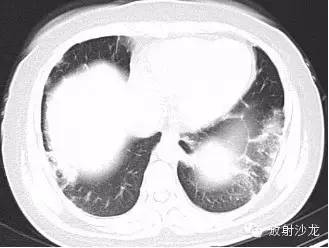

第一例:

44岁女性,因左乳腺结节行胸部CT检查发现胸部病变。

三幅图为典型的胸部结节病表现,肺门纵隔多发淋巴结肿大,各淋巴结不融合、不坏死、不侵犯邻近结构。右侧气管旁、右侧肺门、左侧肺门、主肺动脉窗淋巴结肿大,为1,2,3,4淋巴结。

双肺底见间质性病变。

CT拟诊结节病,呼吸内科建议定期观察。未经任何治疗11个月后复查示肺门纵隔淋巴结正常,双肺底间质性病变消失。左乳腺结节无变化(图略)